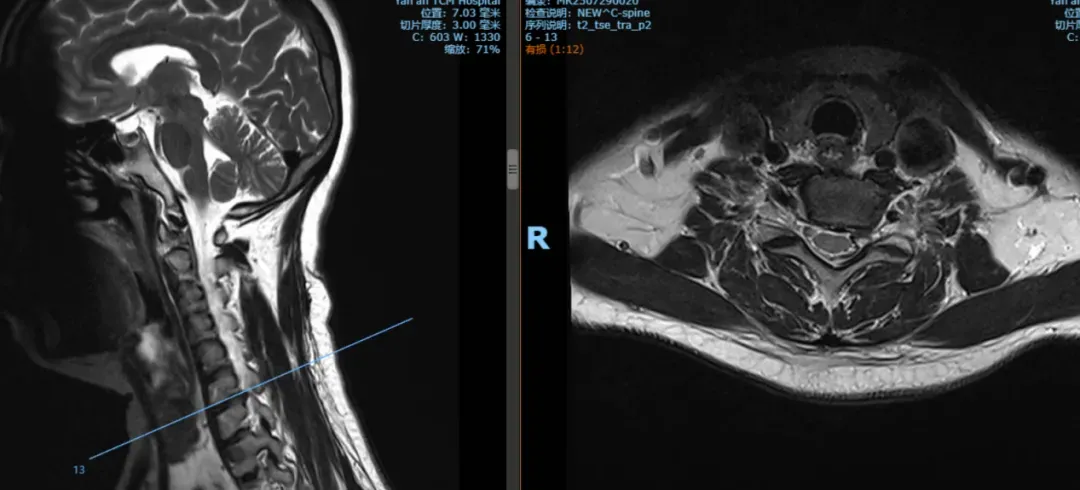

“患者年龄较轻,主要症状为颈肩部疼痛、左上肢麻木,多次反复治疗效果不佳,结合病史、查体及影像学表现,考虑责任节段为颈6-7;症状表现为神经根受压表现,没有脊髓受压表现,为单节段椎间盘突出,突出位于左侧,椎体稳定性尚可。”

术前